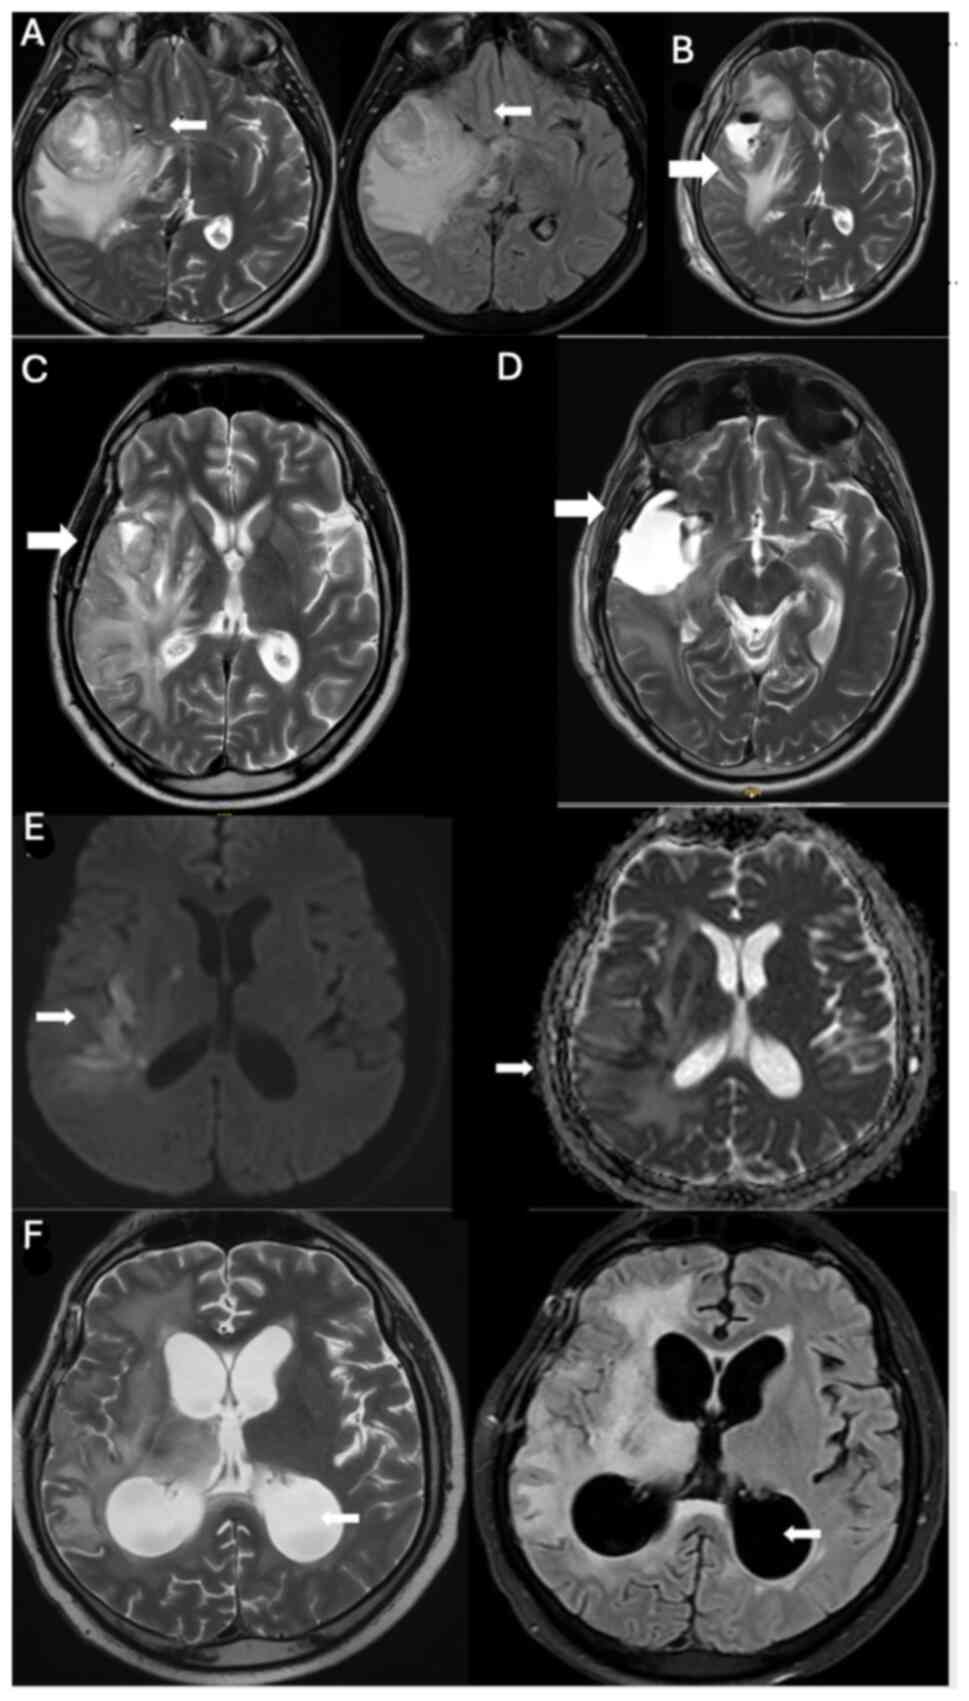

In October 2019 (Fig. 2A), a 42-year-old male patient underwent surgery for an intracranial mass at The Department of Neurosurgery, Hacettepe University Faculty of Medicine, and was diagnosed with glioblastoma, IDH wild-type, WHO grade IV. Immunohistochemical analysis was performed on paraffin-embedded tissue samples using primary antibodies against GFAP, Ki67, IDH1, p53 and ATRX. GFAP staining was positive, ATRX expression was preserved, IDH1 (R132H) and IDH2 were negative, confirming IDH wild-type status. The Ki-67 proliferation index was ~30%, p53 was overexpressed in 10–15% of tumor cells. Total resection was achieved during the operation, as confirmed by pre- and post-operative MRI (Fig. 2A and B). Following surgery, the patient received chemoradiotherapy in the post-operative period. Subsequently, adjuvant temozolomide treatment was initiated in November 2019. An increase in headache complaints was noted after the fifth cycle of temozolomide treatment. The MRI findings were indicative of progression (data not shown).

Figure 2.

(A) A heterogeneous T2 hyperintense tumor with prominent perilesional edema was located in the right fronto-temporo-insular region (white arrows). Additionally, signs of uncal herniation and indentation of the right crus cerebri were evident. (October 2019, before surgery). (B) Postoperative MRI confirming total resection after surgery in October 2019 (white arrow). (C) MRI after two cycles of pembrolizumab, showing progression in June 2020 prior to re-surgery (white arrow). (D) Postoperative MRI in July 2020 after re-surgery, following pembrolizumab treatment (white arrow). (E) Increased signal intensity on diffusion-weighted imaging with corresponding hypointensity on the apparent diffusion coefficient map confirmed the presence of acute ischemia in these areas (white arrows). (F) Triventricular hydrocephalus was visible on T2-weighted imaging and fluid-attenuated inversion recovery imaging in January 2021 (white arrows). A wide T2 hyperintensity in the right fronto-temporo-insular region was also observed. MRI, magnetic resonance imaging.

Before re-surgery, the patient was started on pembrolizumab at a dosage of 200 mg every 3 weeks, and after two cycles of treatment (Fig. 2C), surgical intervention was performed in July 2020 (Fig. 2D). During screening, acute ischemic areas were observed in the right middle cerebral artery territory, with extension into the insular and temporal regions, located at the junction of the right lateral ventricular trunk and the posterior corona radiata (Fig. 2E). Following the surgery, the patient underwent four cycles of pembrolizumab treatment, and cyberknife treatment was administered in September 2020.

As progression was detected, bevacizumab-irinotecan treatment (10 mg/kg bevacizumab, 125 mg/m2 irinotecan, every 2 weeks) was started in September 2020. In January 2021, a cranial MRI (Fig. 2F) performed after four cycles of treatment showed progressive changes. The patient, who had been admitted to the emergency department since that time complaining of continuous seizures, was last observed in the neurosurgical intensive care unit in April 2021 and died in June 2021.